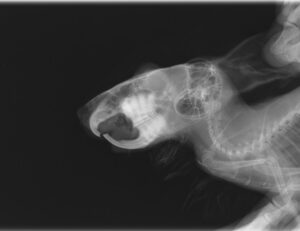

また、併せて歯根の状態の確認のためレントゲン検査を実施します。

レントゲン検査にて、歯根の過長が認められる場合は、神経などを圧迫し痛みを生じるため鎮痛剤を使用することもあります。